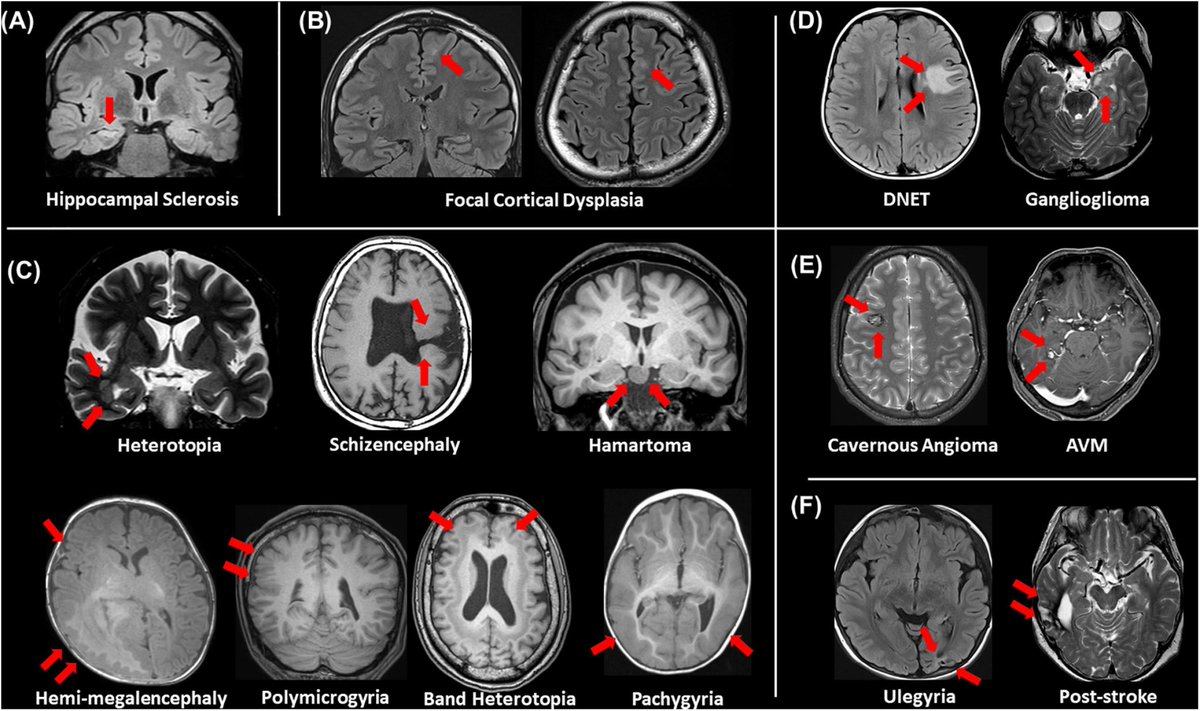

Sometimes epileptogenic lesions are visible on MR(red arrows).We should always keep in mind these lesions first👌 A) Hippocampal sclerosis B)focal cortical dysplasia C) other malformations of cortical development D) neoplasms E) vascular malformations F)cerebrovascular lesions

Sometimes epileptogenic lesions are visible on MR(red arrows).We should always keep in mind these lesions first👌

A) Hippocampal sclerosis B)focal cortical dysplasia C) other malformations of cortical development D) neoplasms E) vascular malformations F)cerebrovascular lesions